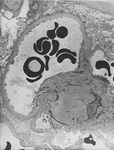

Diabetic kidney disease

Diabetic kidney disease: mesangial expansion is usually recognised when it has exceeded 1.5 times the normal mesangial matrix

From the collection of Dr Raoul Fresco; used with permission